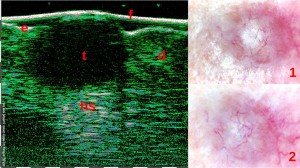

-Μελάνωμα

-Μέτρηση επιπέδων Breslow και Klark σε έμβιο οργανισμό (IN VIVO)

-Διαφοροποίηση τύπων βασικοκυτταρικού καρκινώματος